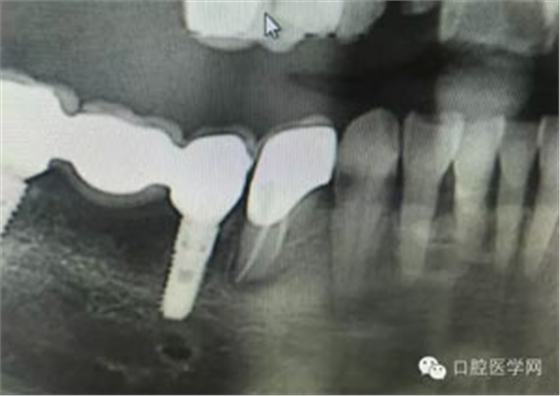

病例1:患者迫切希望保留自己的這一顆牙齒,根尖周陰影比較大,二度松動(dòng).而且旁邊有種植修復(fù)體,和患者溝通好后,治療好后觀察一個(gè)月后冠修復(fù),因?yàn)橛蟹N植的后期修復(fù),所以有了機(jī)會(huì)觀察,術(shù)后三個(gè)月和術(shù)后四個(gè)月,根尖恢復(fù)的還算不錯(cuò),希望能夠繼續(xù)觀察下去.這樣子的病例,做的時(shí)候我們一定要非常的小心,和患者要有充分的溝通以及不同科室的溝通然后決定怎么樣做比較好,假如就是出現(xiàn)了問(wèn)題,到時(shí)候我們也比較好處理些,免得我們自己到時(shí)候不好收?qǐng)觥?/span> 病例2:364647中齲的樹(shù)脂充填,現(xiàn)在樹(shù)脂的充填材料非常之多,有些時(shí)候,我們感覺(jué)有了好的材料我們就可以做出好的修復(fù),可是這是在我們有扎實(shí)的基本功的基礎(chǔ)上的,我們可以沒(méi)有那么好的樹(shù)脂,那么多的顏色選擇,修復(fù)的那么的逼真,但是我們至少要恢復(fù)患者牙齒的功能,將腐質(zhì)去除干凈,薄壁弱尖消除掉,選擇好適應(yīng)癥,給患者以盡可能好的修復(fù)。 來(lái)源于KQ88